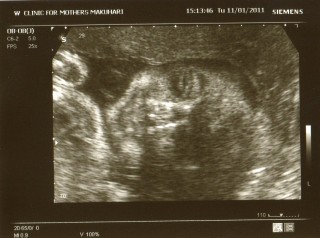

1300gの男の子です。

エコー時は常に顔を隠すシャイな子で

看護士さんに毎回溜息をつかせていましたが

今回、やっと写真が撮れました。

それでもへその緒で少し隠れています(^^;)